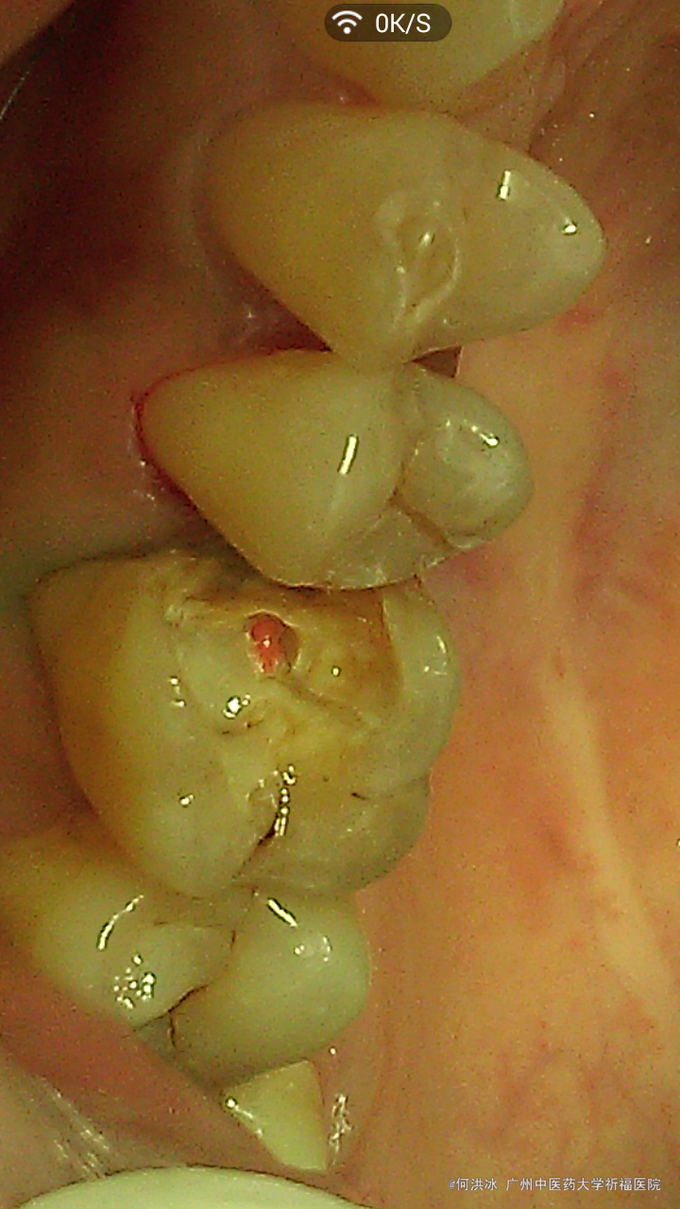

主诉:要求补牙。 病史:女,31岁。右上后牙大牙几年前在外院已做“根管治疗”,当时医生建议做冠,没同意。一直无不适,近日原充填物脱落,进食后易塞食物,要求重补。特别强调,还是不要做冠,不想磨牙太多。

查:16残冠,玻璃粘固粉充填,近中部分脱落,邻接关系不良,有食物嵌入,近中龈乳头轻度压迫性萎缩,轻度充血、红肿。根尖片示根管治疗质量可,根尖区无异常。咬合关系检查,16颊侧微倾,颊侧倒凹较大,颈部有楔缺,部分牙龈萎缩。